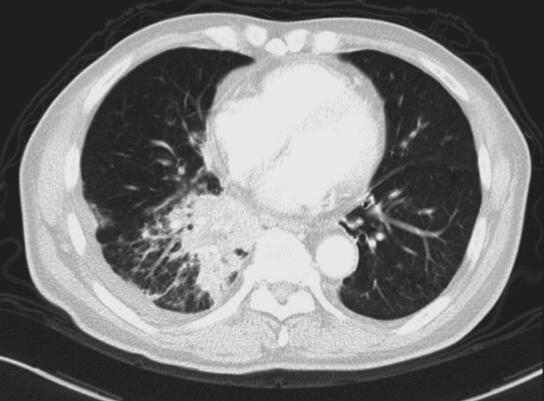

入院后检查:体温36.8℃,脉搏88次/分,呼吸22次/分,血压130/80mmHg。右侧锁骨上可扪及一绿豆大淋巴结,质中,活动度一般,无触痛,其余部位未及明显肿大淋巴结。轻度桶状胸。胸壁无肿块、无扩张血管;呼吸规整,双肺呼吸音粗,可及散在湿啰音及呼气相哮鸣音,未见杵状指(趾),双下肢无水肿。血常规正常、生化正常、肝炎标志物、梅毒+HIV抗体均阴性;类风湿因子、风湿因子阴性、结核抗体:阴性;8次结核涂片:荧光染色抗酸杆菌(-);G试验、血隐球菌乳胶凝集试验、血寄生虫抗体均阴性;3次痰涂片革兰染色未见细菌;血T-spot:(A抗原)20个、(B抗原)3个;血CD4+/CD8+正常。血管紧张素转化酶32IU/ L。肺功能:通气功能轻度减退(阻塞性),残气及残总比值增高,弥散轻度减退,气道阻力增高。FVC 2.16L(95.3%);FEV1 1.22L(69.4%);FEV1/FVC 56.72%。胸CT(2014年4月17日)示:两肺肺气肿,右肺下叶见团片状病灶,纵隔、肺门多发淋巴结肿大(图1和图2)。右下肺穿刺:见少许炎性细胞。右锁骨上淋巴结穿刺见少量炎性细胞及上皮样细胞。气管镜左总支气管新生物活检:重度慢性炎。气管镜右中间支气管刷检灌洗找结核肿瘤(-)。气管镜1R、2R、7组淋巴结E-bus穿刺见炎性细胞及少量坏死组织。

图1 2014年4月17日胸部CT

肺窗见右肺下叶见团片状病灶